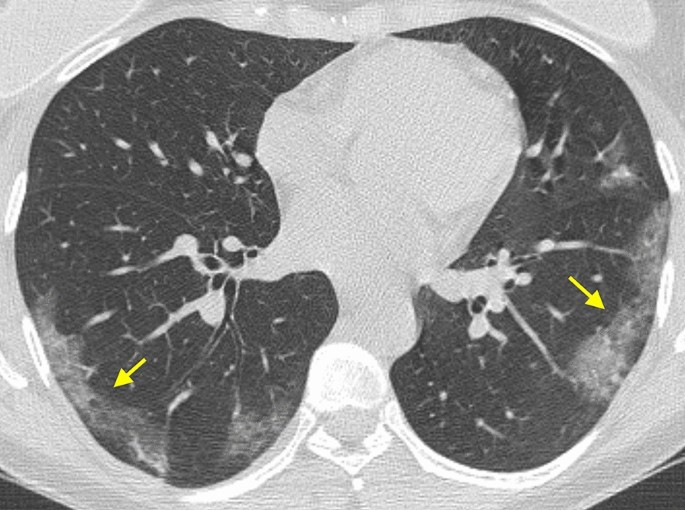

Covid19

Covid 19 Appearance On Ct